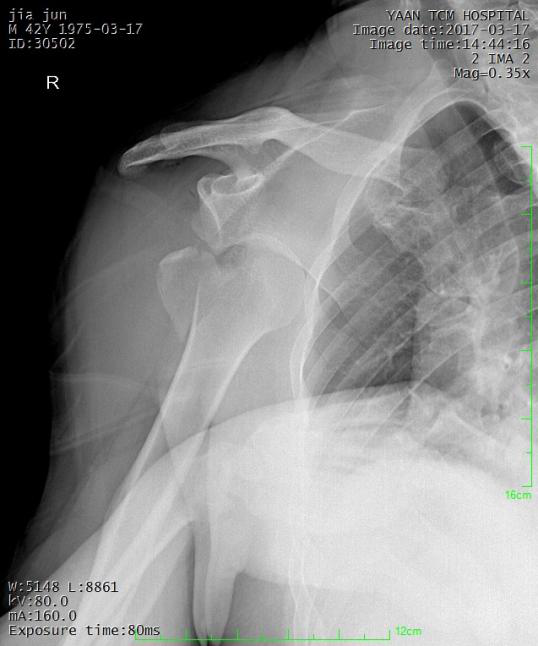

常见骨折手法整复:

桡骨下端骨折

术前: